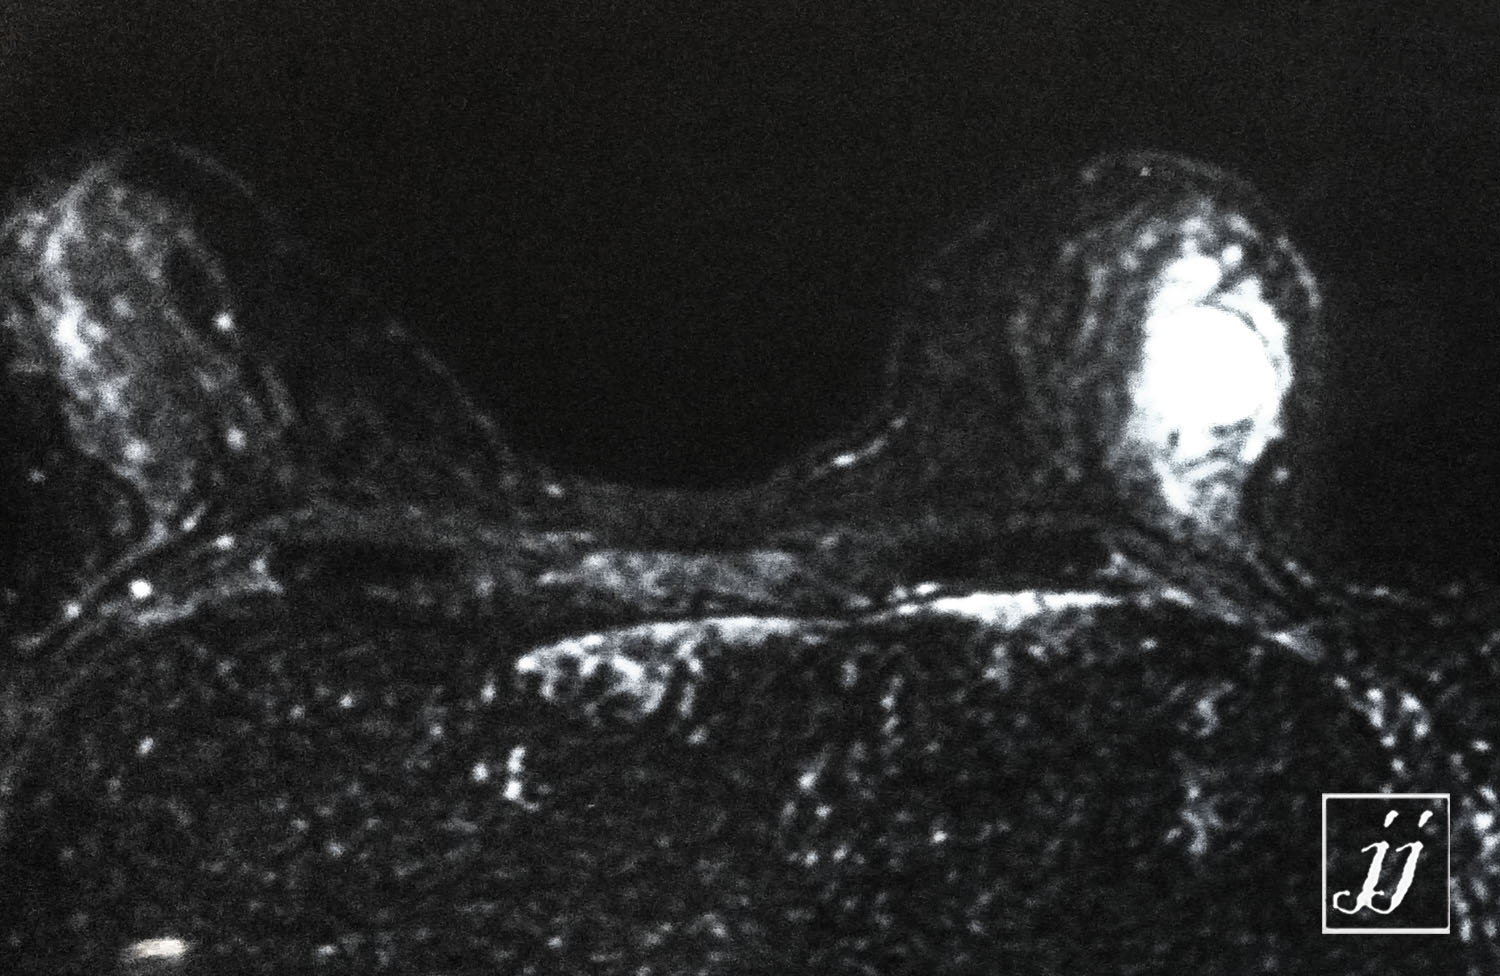

Breast- left breast enhanced mass (3)